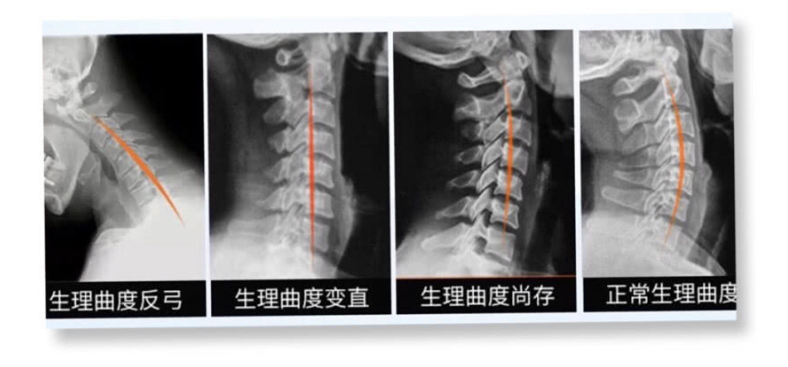

全職麻麻這兩年,陪娃帶娃總是低著頭,好不容易寶寶睡了有自己時間了忍不住低頭玩手機,結(jié)果我天天脖子痛的厲害,去醫(yī)院診斷為頸椎反弓,正常頸椎的生理曲度應(yīng)該是向前彎曲,如果長期不良姿勢會導(dǎo)致曲度變直然后是反弓,我當時覺得很嚴重問醫(yī)生咋辦。醫(yī)生淡淡的說:沒有辦法現(xiàn)在大家頸椎強直的,反弓的太多了,最普遍和嚴重的原因就是長期的低頭玩手機。

生理曲度的改變醫(yī)生們也沒有辦法,不可能做手術(shù)吧,一般會建議你做康復(fù)治療,就是經(jīng)常去醫(yī)院做頸部牽引之類得長期堅持不然效果不大,那么到底怎么才能改變回正常的生理曲度呢?

頸椎生理曲度